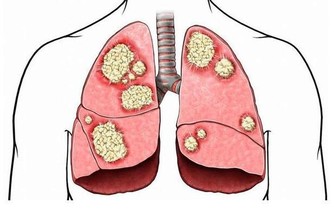

“嫌貧愛富”,我們常用來形容對人的好惡以其貧富為準。但有一種癌症,它也具有這種特性,那便是大腸癌。

大腸癌是與飲食習慣密切相關的疾病,隨著經濟水平提高,生活富裕,食物越多,吃得越好,大腸癌也變得越“活躍”。在我國,每年有14萬人被確診患大腸癌,而且發病率每年遞增2.5%~5.0%,遠遠高於全球平均水平的2%。

及時發現和治療,90%的大腸癌患者可以得救。所以,定期體檢很重要!

建議:一般人群50歲開始接受大腸癌的篩查,每5~10年進行一次檢查,檢查主要包括大便隱血和腸鏡。高危人群可提前到40~45歲左右,平均每3~5年接受一次檢查。